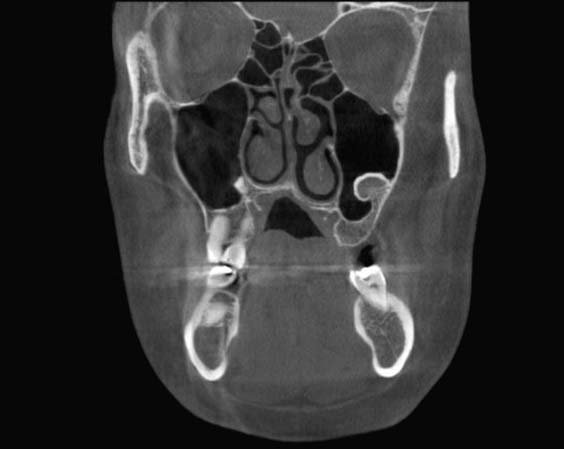

La Tomografía Computarizada Cone Beam (TCCB) es una tecnología en rápido desarrollo que proporciona imágenes de alta resolución espacial del complejo craneofacial en tres dimensiones (3D).